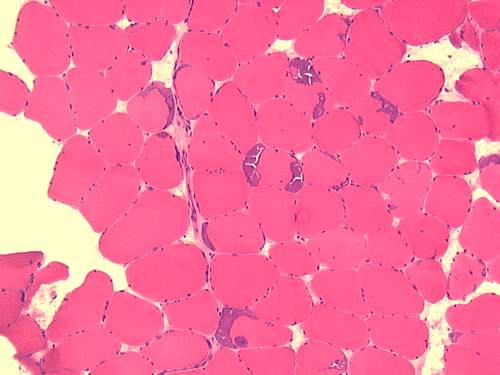

Pathology of the case: On hematoxylin-eosin stained frozen sections, there are many stongly basophilic, irregular subsarcolemmal depositions (Panel A and B). There is no significant variation in fiber diameter, increase in centrally located nucleus, inflammation, necrotic fiber, regenerating fibers or target fibers. These deposits appear bright red on modified Gomori's trichrome (Panel C). On ATPase reaction at pH 4.6 (dark fibers are type 1, pale fibers are type 2a while intermediate-intensity fibers are type 2b), there is no fiber type predominance (Panel D). Although the deposits are not visualized in the ATPase preparation, they are strongly reactive in NADH-TR reaction. Intesestingly, these deposits are not visualized in another preparation of oxidative enzyme- succinate dehydrogenase (Panel F). On the adenylate deaminase preparation, these deposits are strongly reactive (Panel G). The subsarcolemmal deposits are well visualized under the electron microscope which is electron dense (Panel H). On cross sections, these deposits are bundles of densely packed polygonal to round tubules with double walls that are arranged in small fascicles (Panel  I and J). The tubules are about 50-80 nm in diameter. The tubular aggregates also arrange in longitudinal bundles that run along the myofibrils (Panel K).

Tubular aggregates are well demonstrated in many routinely used histochemical stain. In general, tubular aggregates appear as irregular, subsarcolemmal depositions 4. They appear bright red in modified Gomori's trichrome. These aggregates appear strongly basophilic on hematoxylin-eosin stained frozen sections but they are quite indistinctive in paraffin embedded sections stained with hematoxylin-eosin. The aggregates appear intensely dark blue on NADH-TR reactions and this feature lead to the early impression that they are derived from the mitochondria. However, their lack of succinate dehydrogenase. Tubular aggregates are also strongly positive for lactate dehydrogenase and adenylate deaminase. These features argue against a mitochondrial origin.  Tubular aggregates are usually but not invariably found in type II fibers.